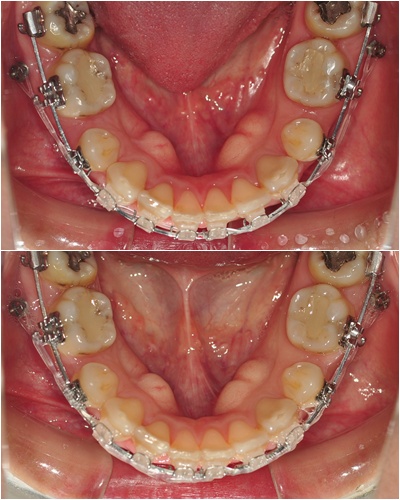

4주동안 얼마나 달라졌는지~ 비교사진 나갑니다~ ㅇㅅㅇ)!!

└▷ 잠시 쉬었었던 파워체인 연결을 다시 하니 발치공간이 또 조금씩 줄어들기 시작했어요~

└▷ 상악 발치공간은 아직 그대로네요~ 그래도 공간이 얼마 안남았으니 괜찮아요~ ㅋㅋ